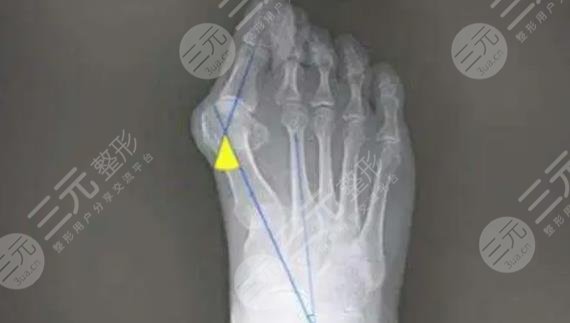

蘇敬達(dá):蘇敬達(dá)醫(yī)生畢業(yè)于河北醫(yī)科大學(xué)臨床醫(yī)學(xué)系,此后又到中南民族醫(yī)學(xué)院進(jìn)修碩士,是國(guó)際acid的高級(jí)足部整形醫(yī)生,專注于做微創(chuàng)美足精雕項(xiàng)目。從事足部整形已有多年時(shí)間了,也是國(guó)內(nèi)較早一批從事足部整形的專家,對(duì)于拇指外翻微創(chuàng)緩解、長(zhǎng)指縮短、足趾纖細(xì)術(shù)等都擁有豐富的臨床工作經(jīng)驗(yàn),對(duì)于有足部整形訴求的小伙伴來說,蘇醫(yī)生是值得大家去詳細(xì)了解的醫(yī)生哦~

手術(shù)前:作為一個(gè)女生都想要穿高跟鞋吧,我特別喜歡穿高跟鞋,但是不知道是長(zhǎng)期穿高跟鞋的原因,還是天生就這樣,我的大拇指外翻還蠻嚴(yán)重的,很影響我的腳形美觀,而且穿高跟鞋會(huì)特別的痛,所以在幾番糾結(jié)之后,還是決定做大腳骨手術(shù)。也希望自己能夠擁有好看的足部形態(tài),至少穿高跟鞋的時(shí)候別讓我痛吧~

手術(shù)后:在做完手術(shù)之后,我一直都堅(jiān)持著良好的作息習(xí)慣去恢復(fù),整體來說,恢復(fù)的過程還是蠻快的。目前效果我很滿意,大腳骨已經(jīng)有了特別明顯的改良,也沒有拇指外翻的現(xiàn)象了,特別開心,確實(shí)也沒有想到這個(gè)效果會(huì)這么好,開始我以為減輕一點(diǎn)就不錯(cuò)了,沒想到一次手術(shù)就讓我恢復(fù)了正常腳趾的狀態(tài)。